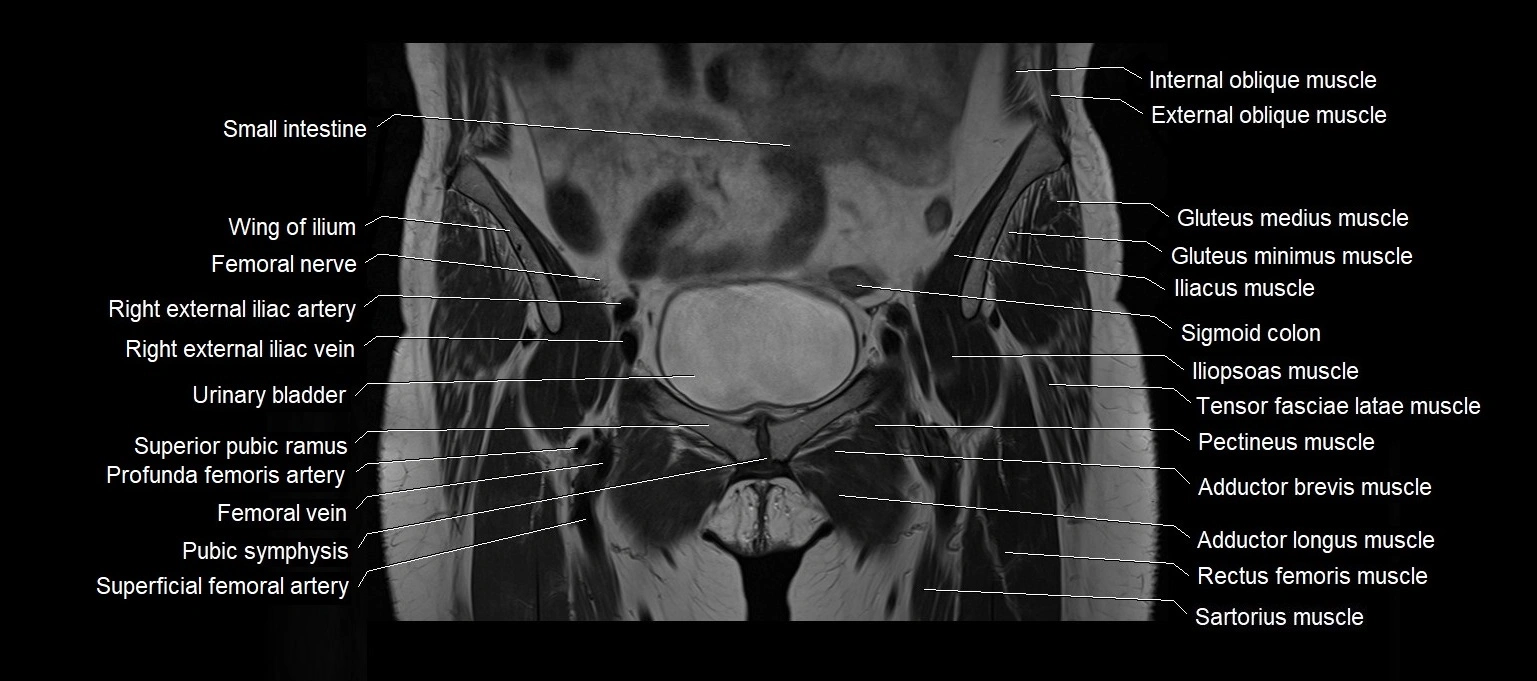

- External iliac artery

- External iliac vein

- Femoral nerve

- Femoral vein

- Iliopsoas muscle

- Pectineus muscle

- Pubic symphysis

- Pyramidal muscle (pyramidalis muscle)

- Rectus femoris muscle

- Sartorius muscle

- Sigmoid colon

- Superior pubic ramus

- Tensor fasciae latae muscle

- Urinary bladder